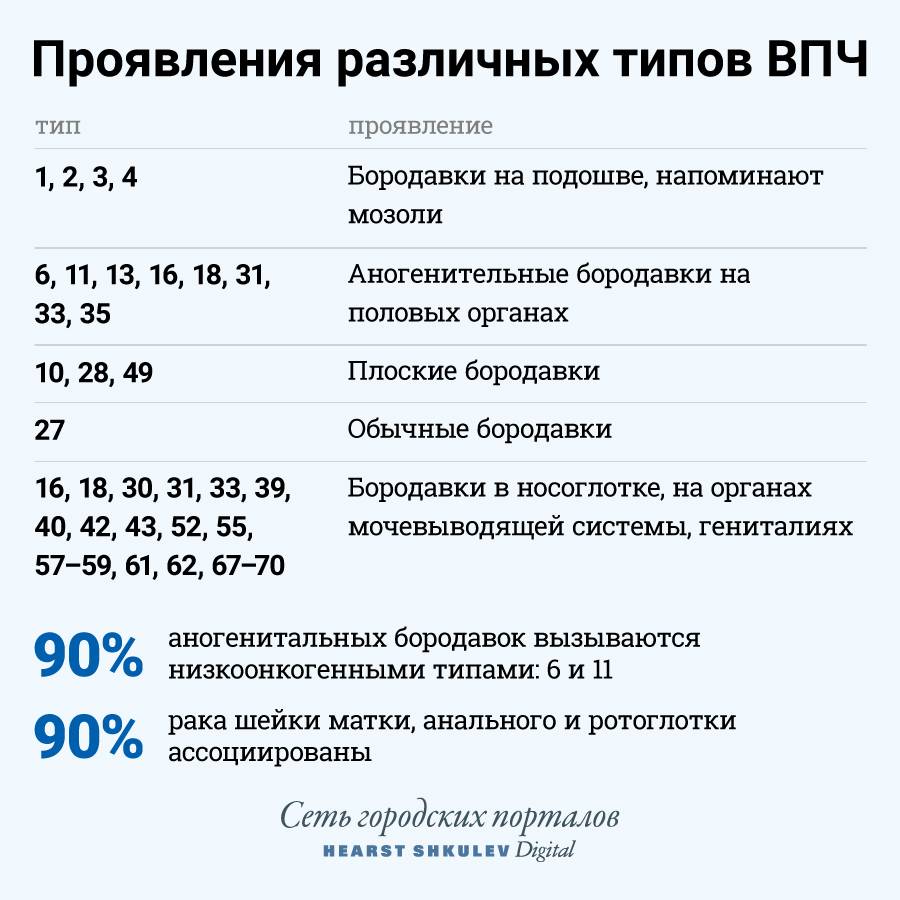

Кондиломы - это одно из самых распространенных заболеваний, передающихся половым путем. Они вызваны вирусом папилломы человека (ВПЧ) и могут появляться на внешних половых органах, анусе, ротовой полости и других областях тела.

Симптомы кондилом могут варьироваться, и визуальное представление этого заболевания может быть различным. Некоторые кондиломы выглядят как небольшие бугорки или бородавки, в то время как другие могут иметь форму плоских пятен или цветных наростов.